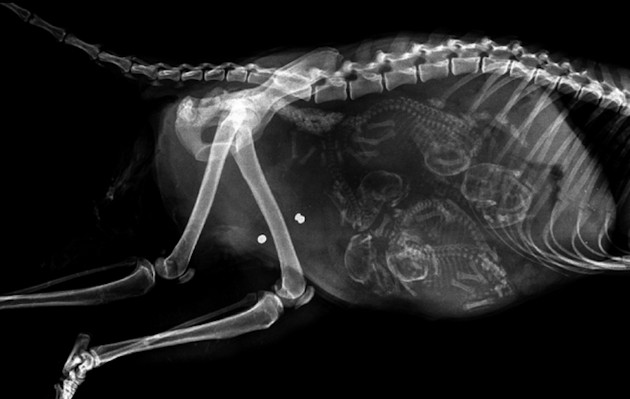

Radostné očakávanie môže u rôznych zvieracích druhov vyzerať všelijako. Fotky, ktoré vám dnes ukážeme sú raritné a rozhodne zaujímavé. Predsa len, videli ste už niekedy tehotné zvieratá cez röntgenové snímky?

Niektoré z nich rodia živé mláďatá, iné zasa kladú vajíčka. Zrod nového života vo zvieracej ríši je každopádne fascinujúci. A ako vyzerajú tehotné zvieratká sa môžete pozrieť na nasledujúcich “lekárskych” snímkoch.

Činčila